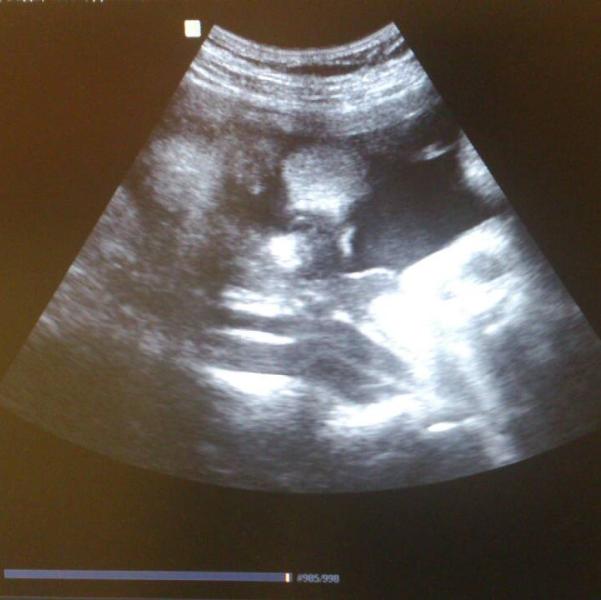

сходила на третий скрининг:-) фото называется найди ребенка:-D

Вспомнила сериал друзья😀, там рейчел психовала что не может увидеть ребёнка 😂

@irinyshka Ахах бывает, но тут точно лицо мелкой, просто плохо видно.

пухленькие щеки 😊 я увидела 😁